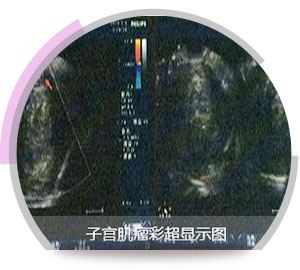

河南医药院专家董长江教授耐心的接待并做了详细检查,彩超、子宫输卵管造影及宫腹腔镜检查。

彩超检查证实盆腔左侧有一直径4*5cm卵巢囊块,呈一中高回声表现,确诊卵巢囊肿,子宫输卵管造影发现其子宫内低回声,有5*6cm巨大肿瘤,确诊子宫肌瘤,且患者有高血压。